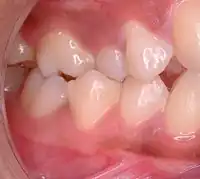

| Malocclusion in 10-year-old girl | |

In orthodontics, a malocclusion is a misalignment or incorrect relation between the teeth of the upper and lower dental arches when they approach each other as the jaws close. The English-language term dates from 1864;[1] Edward Angle (1855–1930), the "father of modern orthodontics",[2][3] popularised it. The word derives from mal- 'incorrect' and occlusion 'the manner in which opposing teeth meet'.

The malocclusion classification is based on the relationship of the mesiobuccal cusp of the maxillary first molar and the buccal groove of the mandibular first molar. If this molar relationship exists, then the teeth can align into normal occlusion. According to Angle, malocclusion is any deviation of the occlusion from the ideal.[4] However, assessment for malocclusion should also take into account aesthetics and the impact on functionality. If these aspects are acceptable to the patient despite meeting the formal definition of malocclusion, then treatment may not be necessary. It is estimated that nearly 30% of the population have malocclusions that are categorised as severe and definitely benefit from orthodontic treatment.[5]